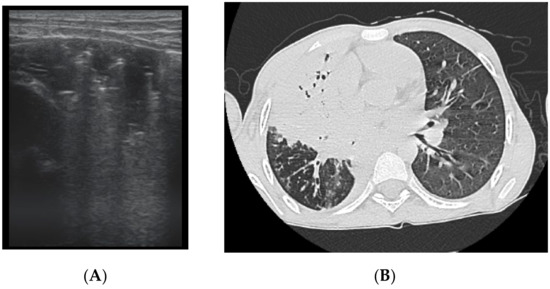

The artefacts used to define the pathological elements were as follows (Table 1): the presence of A lines—normal aspect = 0 points; less than 3 B lines, thin (< 2 mm in width)/intercostal space = 0 points; more than 3 distinctive B lines or 1 coalescent B line = 1 point, quantifying interstitial inflammation or small bronchiectasis (Figure 1) confirmed by CT (Figure 2); more than 2 coalescent B lines = 2 points, suggestive of alveolo-interstitial inflammation or mucus plugging with loss of aeration; either bronchial wall thickening or subpleural consolidation < 1 cm = 3 points, associated with the absence of A lines quantified either as small atelectasis or cystic bronchiectasis with mucus plugging; subpleural lung consolidation > 1 cm, without bronchogram = 4 points; quantified atelectasis (Figure 3)/consolidation with bronchogram = 5 points.

Figure 1. LUS image shows B lines > 3, LUS score = 2. The corresponding CT image (Figure 2) shows bronchiectasis.

Figure 2. CT reveals (1) peripheral cylindrical bronchiectasis with mucus plugging.